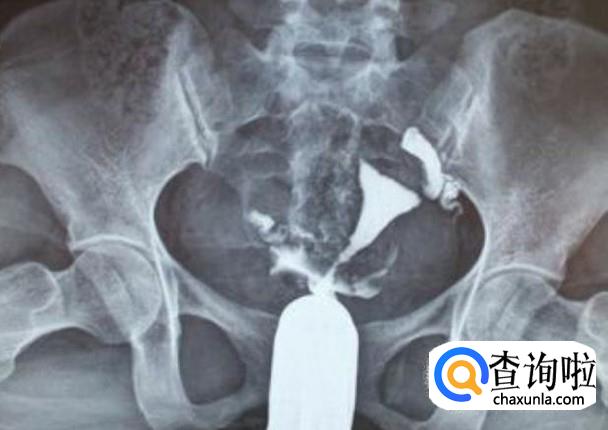

在x线下观察造影剂充盈宫颈、子宫及双侧输卵管时的形态,了解输卵管是否通畅,还有通过摄像,看到输卵管堵塞的大概位置。